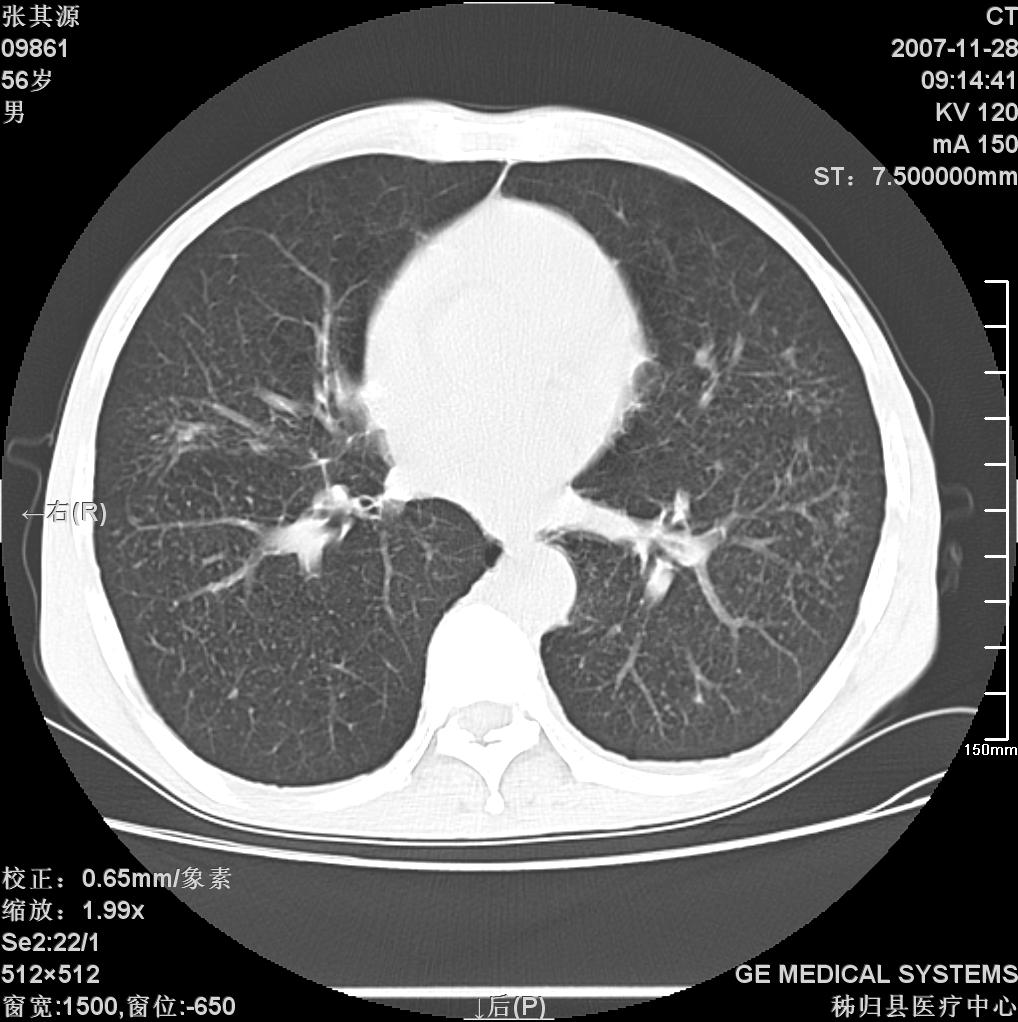

患者因阻塞性黄疸入院,发病前10天持续中等程度发烧.术前检查发现两肺弥漫性病变,请各位大虾会诊,除了考虑急性血源性肺结核外,还有其他什么疾病可能.

影像符合粟粒型肺tb改变。

双肺多发粟粒样病灶,右肺胸膜下结节样病灶,气管前腔静脉后及隆突下均见肿大淋巴结,结合胆道肿瘤病史首先考虑转移。另外心影密度略低,时间格显示,是否有贫血?查明白再手术吧!

两肺另见略大结节,结合病史,应考虑转移,有腹部片吗?肺内表现可有:结核?甲状腺癌肺转移?肺泡癌?